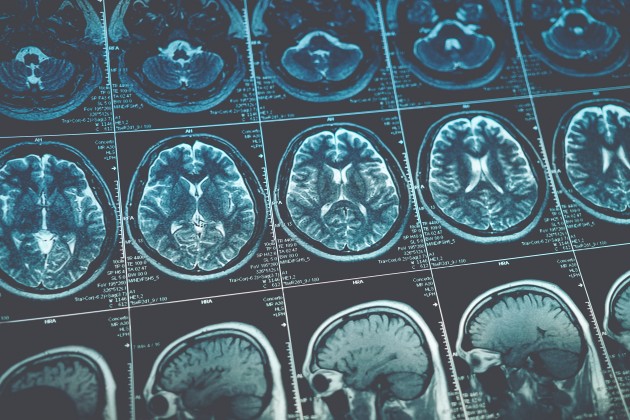

Dr Josh conducted brain scans on the 49 inmates and found out two things:

"In this most recent paper, we are able to look at brain-based measures of reward and value and the communication between different brain regions that are involved in decision making.